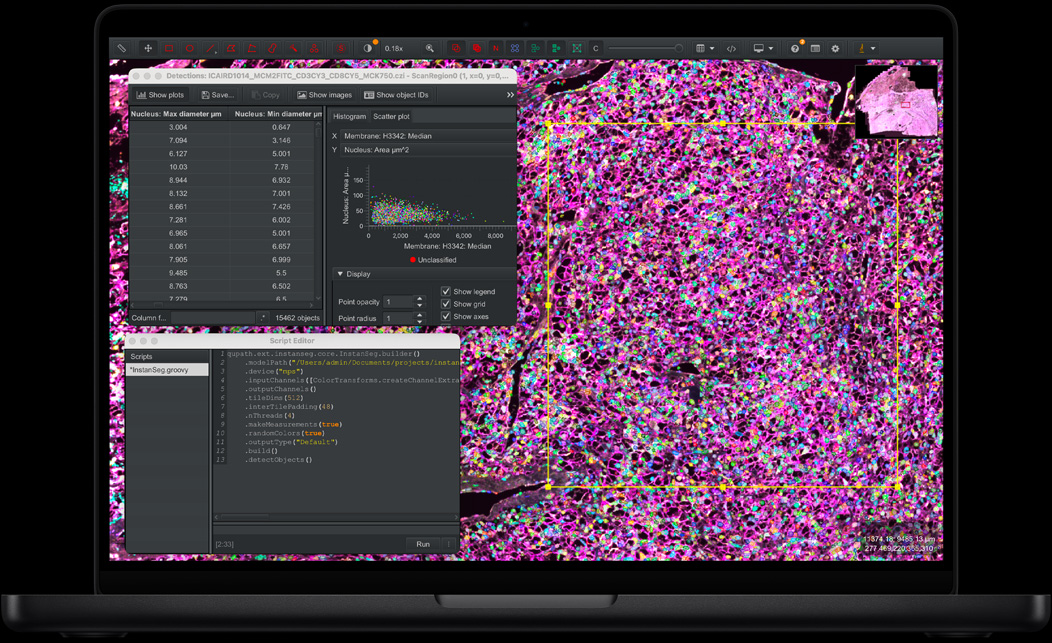

M5 Pro delivers even more power for scientists, engineers, software developers, and creative pros tackling intensive projects.

For those who push the limits, M5 Pro speeds up everything from compiling code to sequencing DNA to editing multiple streams of 8K ProRes video. Whether you choose the 14- or 16-inch model, MacBook Pro with M5 Pro handles demanding workflows and AI-based tasks with ease. Its up to 20-core GPU delivers eye-opening graphics performance for faster 3D rendering and animation. And with starting storage doubled, now 1TB and up, you have even more room to work wonders.

QuPath, Instanseg